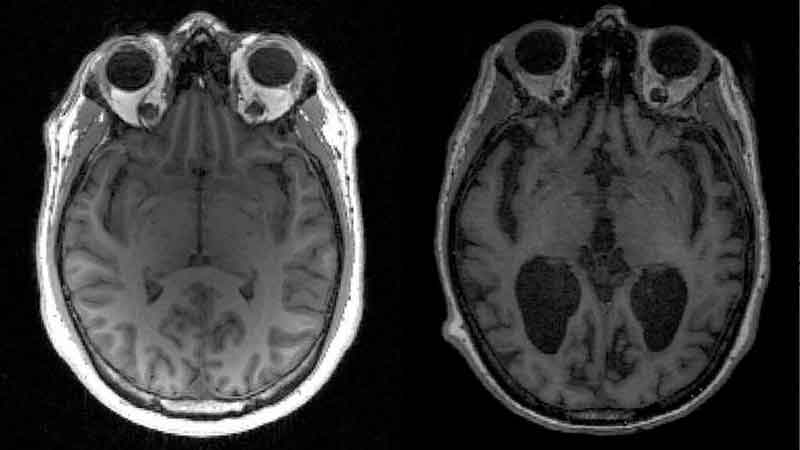

O Alzheimer é uma doença neurodegenerativa caracterizada pelo comprometimento da memória e da capacidade de realizar tarefas cotidianas. O diagnóstico clínico geralmente ocorre tarde (quando o paciente já apresenta lapsos de memória), embora os mecanismos de ação da doença estejam presentes anos antes do aparecimento dos primeiros sintomas.